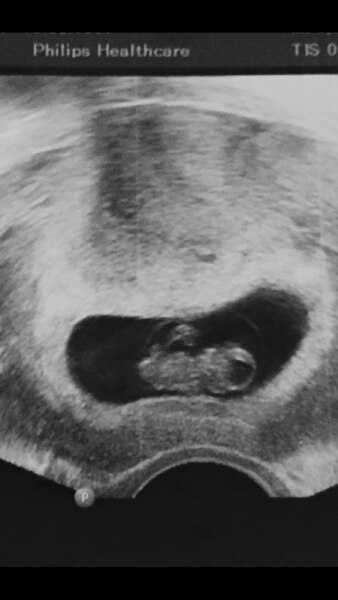

Da hat er sich sixher vertan ich war bei der untersuchung 13 ssw und das baby war 6.12cm groß

Bild zu